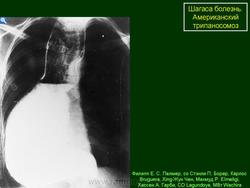

На протяжении второй стадии паразиты концентрируются, в основном, в сердце или мускулатуре пищеварительного тракта. До 30% пациентов страдает от нарушений сердечной деятельности и до 10% – от изменений в органах пищеварения (характерна гипертрофия пищевода или толстой кишки), нервной системе или целом ряде органов. В последующие годы инфекция может приводить к внезапной смерти или сердечной недостаточности, вызываемой прогрессивным разрушением сердечной мышцы.